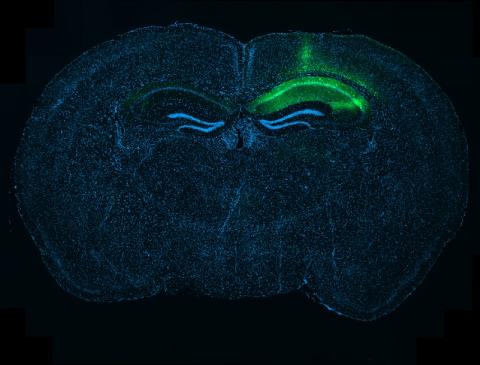

In the Alzheimer’s brain, there is a build-up of abnormal proteins in and around the cells, known as amyloid beta and tau. These stick together to form structures known as amyloid beta plaques and tau neurofibrillary tangles. These structures are linked to poor functioning, and the eventual loss, of neurons, which leads to the gradually worsening symptoms of the condition.

The main pathological protein hallmarks of Alzheimer's - amyloid beta plaques and tau neurofibrillary tangles. Credit: NIH.